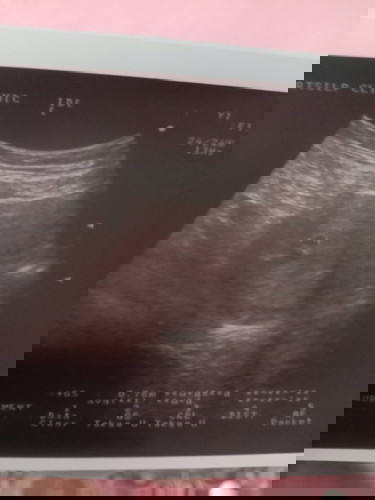

แม่บ้านนี้รุ้ว่าท้องพอได้สักอาทิตย์1ก็มีเลือดออกนิดหน่อยแต่ไม่ปวดท้อง ไปหาหมอที่คลินิคหมอซาวแล้วบอกว่าน่าจะเป็นแท้งคุกคามตอนไปหาหมอได้6วีคแล้ว ซาวแล้วเจอถุงการตั้งครรภ์แต่ไม่เจอเด็กและเจอรอยเลือดออกที่หลังถุงการตั้งครรภ์ หมอเลยฉีดยากันแท้งให้1เข็ม เลือดก็หยุดไหล หมอเลยนัดดูอีก2อาทิตย์ก็คือวันนี้ พอไปซาวก้ยังไม่เจอตัวเด้กแต่ถุงการตั้งครรภ์ขยายใหญ่ขึ้นว่าเดิม2-3เซน ตอนแรก7เซน ไปรอบสอง9-10เซน แต่ก้ยังเจอรอยเลือดหลังถุงการตั้งครรภ์เหมือนเดิม หมอบอกอาจจะเป็นรอยเก่า และอาจจะเป็นท้องลม #มีแม่ๆบ้านไหมเป็นแบบนี้แล้วเจอตัวเด็กบ้างไหมค่ะ #เจอเด็กตอนกี่วีคค่ะ😔😔กังวลมากเลยค่ะหมอนัดวันจันทร์หน้าอีกทีค่ะ